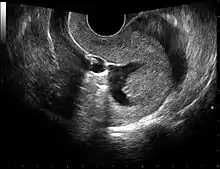

![]() Left hydrosalpinx on gynecologic ultrasonography | |